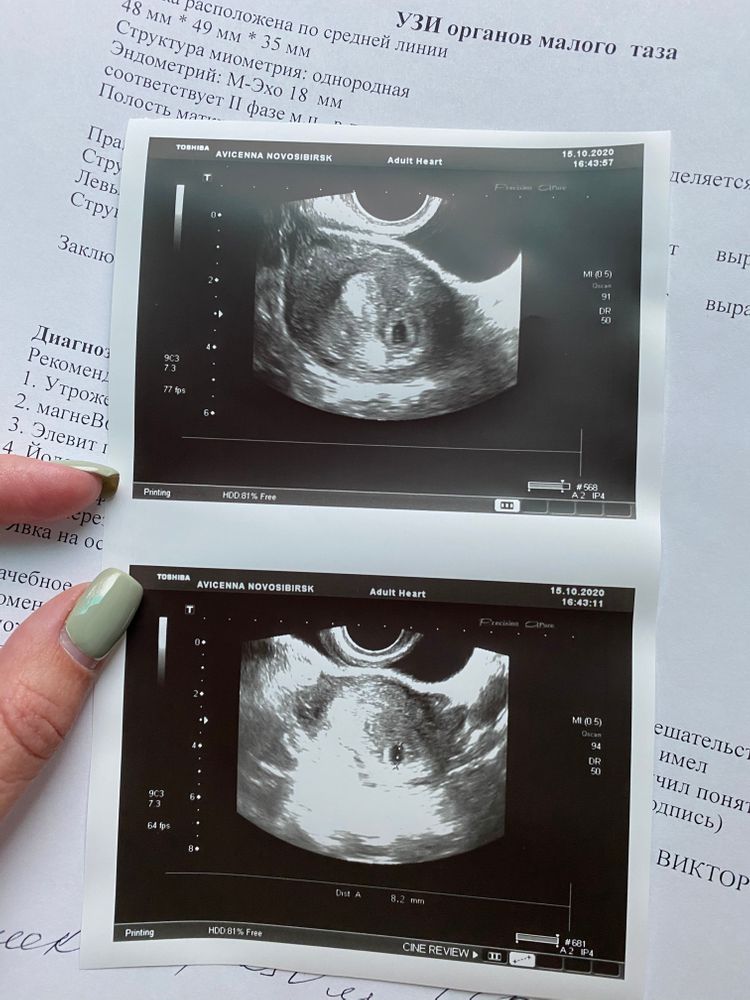

Наше первое узи

У нас сегодня было первое узи ☺️

Мы прикрепились там где нужно, в положенном месте 🤞🏼